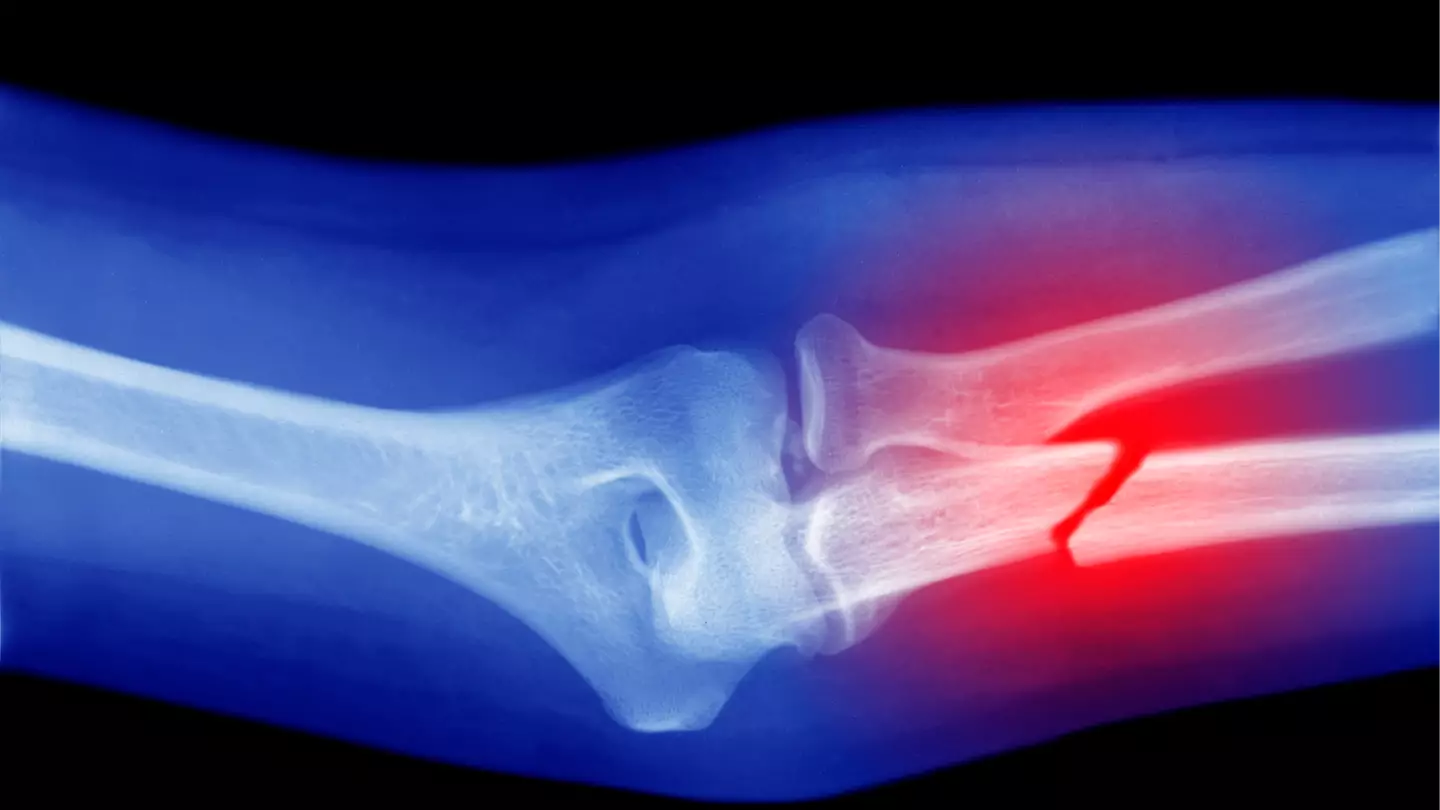

Why some people more likely to break a bone, explained

"We all know people who seem to trip and fall frequently but then bounce back up, and laugh it off," Dr Hussain recently told LADbible, adding: "Conversely, someone else trips over a curb and ends up in a cast."

"So why does this happen? Turns out, it’s not all random or down to divine protection," he continued.